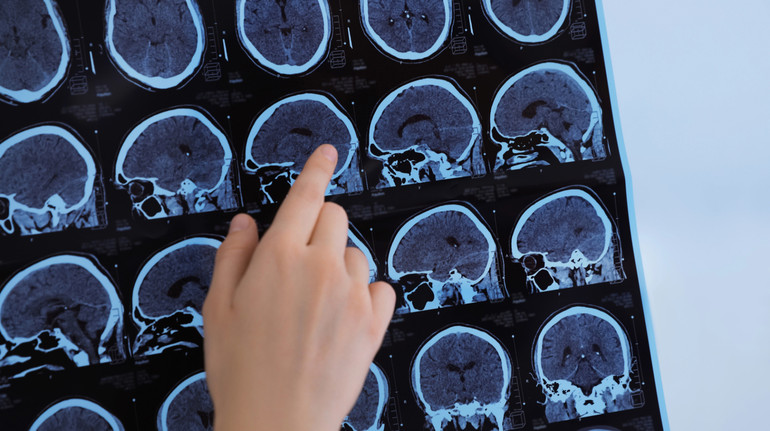

Вчені виявили два нові підтипи розсіяного склерозу – хронічного аутоімунного захворювання центральної нервової системи. У цьому їм допомогли штучний інтелект, аналіз крові та магнітно-резонансна терапія (МРТ).

Результати аналізу sNfL разом зі сканами мозку пацієнтів інтерпретувала модель машинного навчання SuStaIn. Так, команда виявила два чіткі типи розсіяного склерозу – з раннім і пізнім підвищенням sNfL.